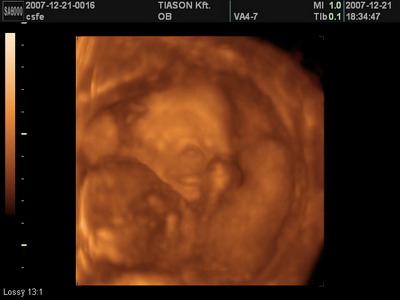

Én már 11X végénél tartok. (mentségemre legyen mondva ketten laknak a pocakomban) De az előzmények hasonlóak, és nálam is pont +5kg.